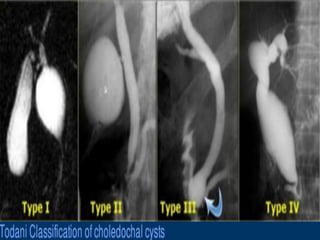

Todani classification

In adult patients, a choledochal cyst is often first diagnosed on cross-

sectional imaging.

CT and ultrasound demonstrate a fluid-filled structure beneath the

porta hepatis separate from the gallbladder that communicates with the

hepatic ducts.

An abrupt change in the caliber of the ducts occurs at the site of the

cysts.

Intrahepatic ductal dilatation may be present as well.